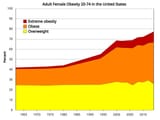

>almost 70 PERCENT of women are OBESE